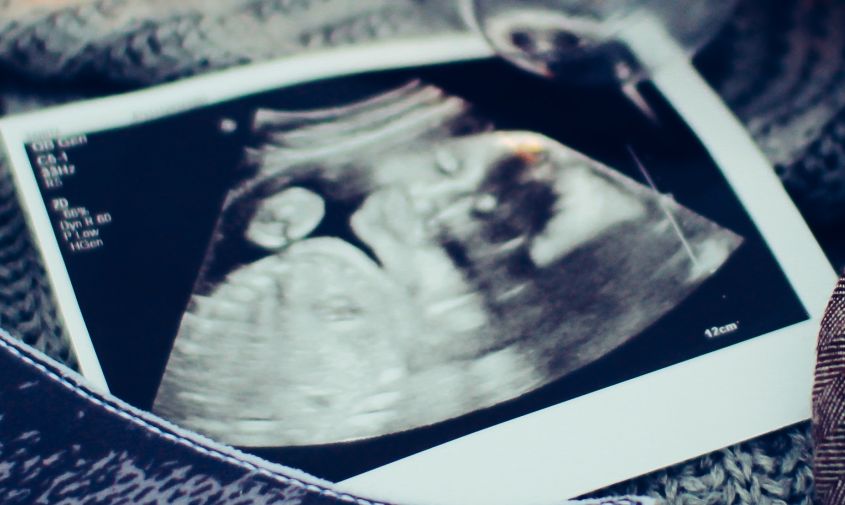

В разделе, посвященном инструментальным исследованиям, врачам рекомендуют при УЗИ плода демонстрировать женщинам его изображение и сердцебиение.